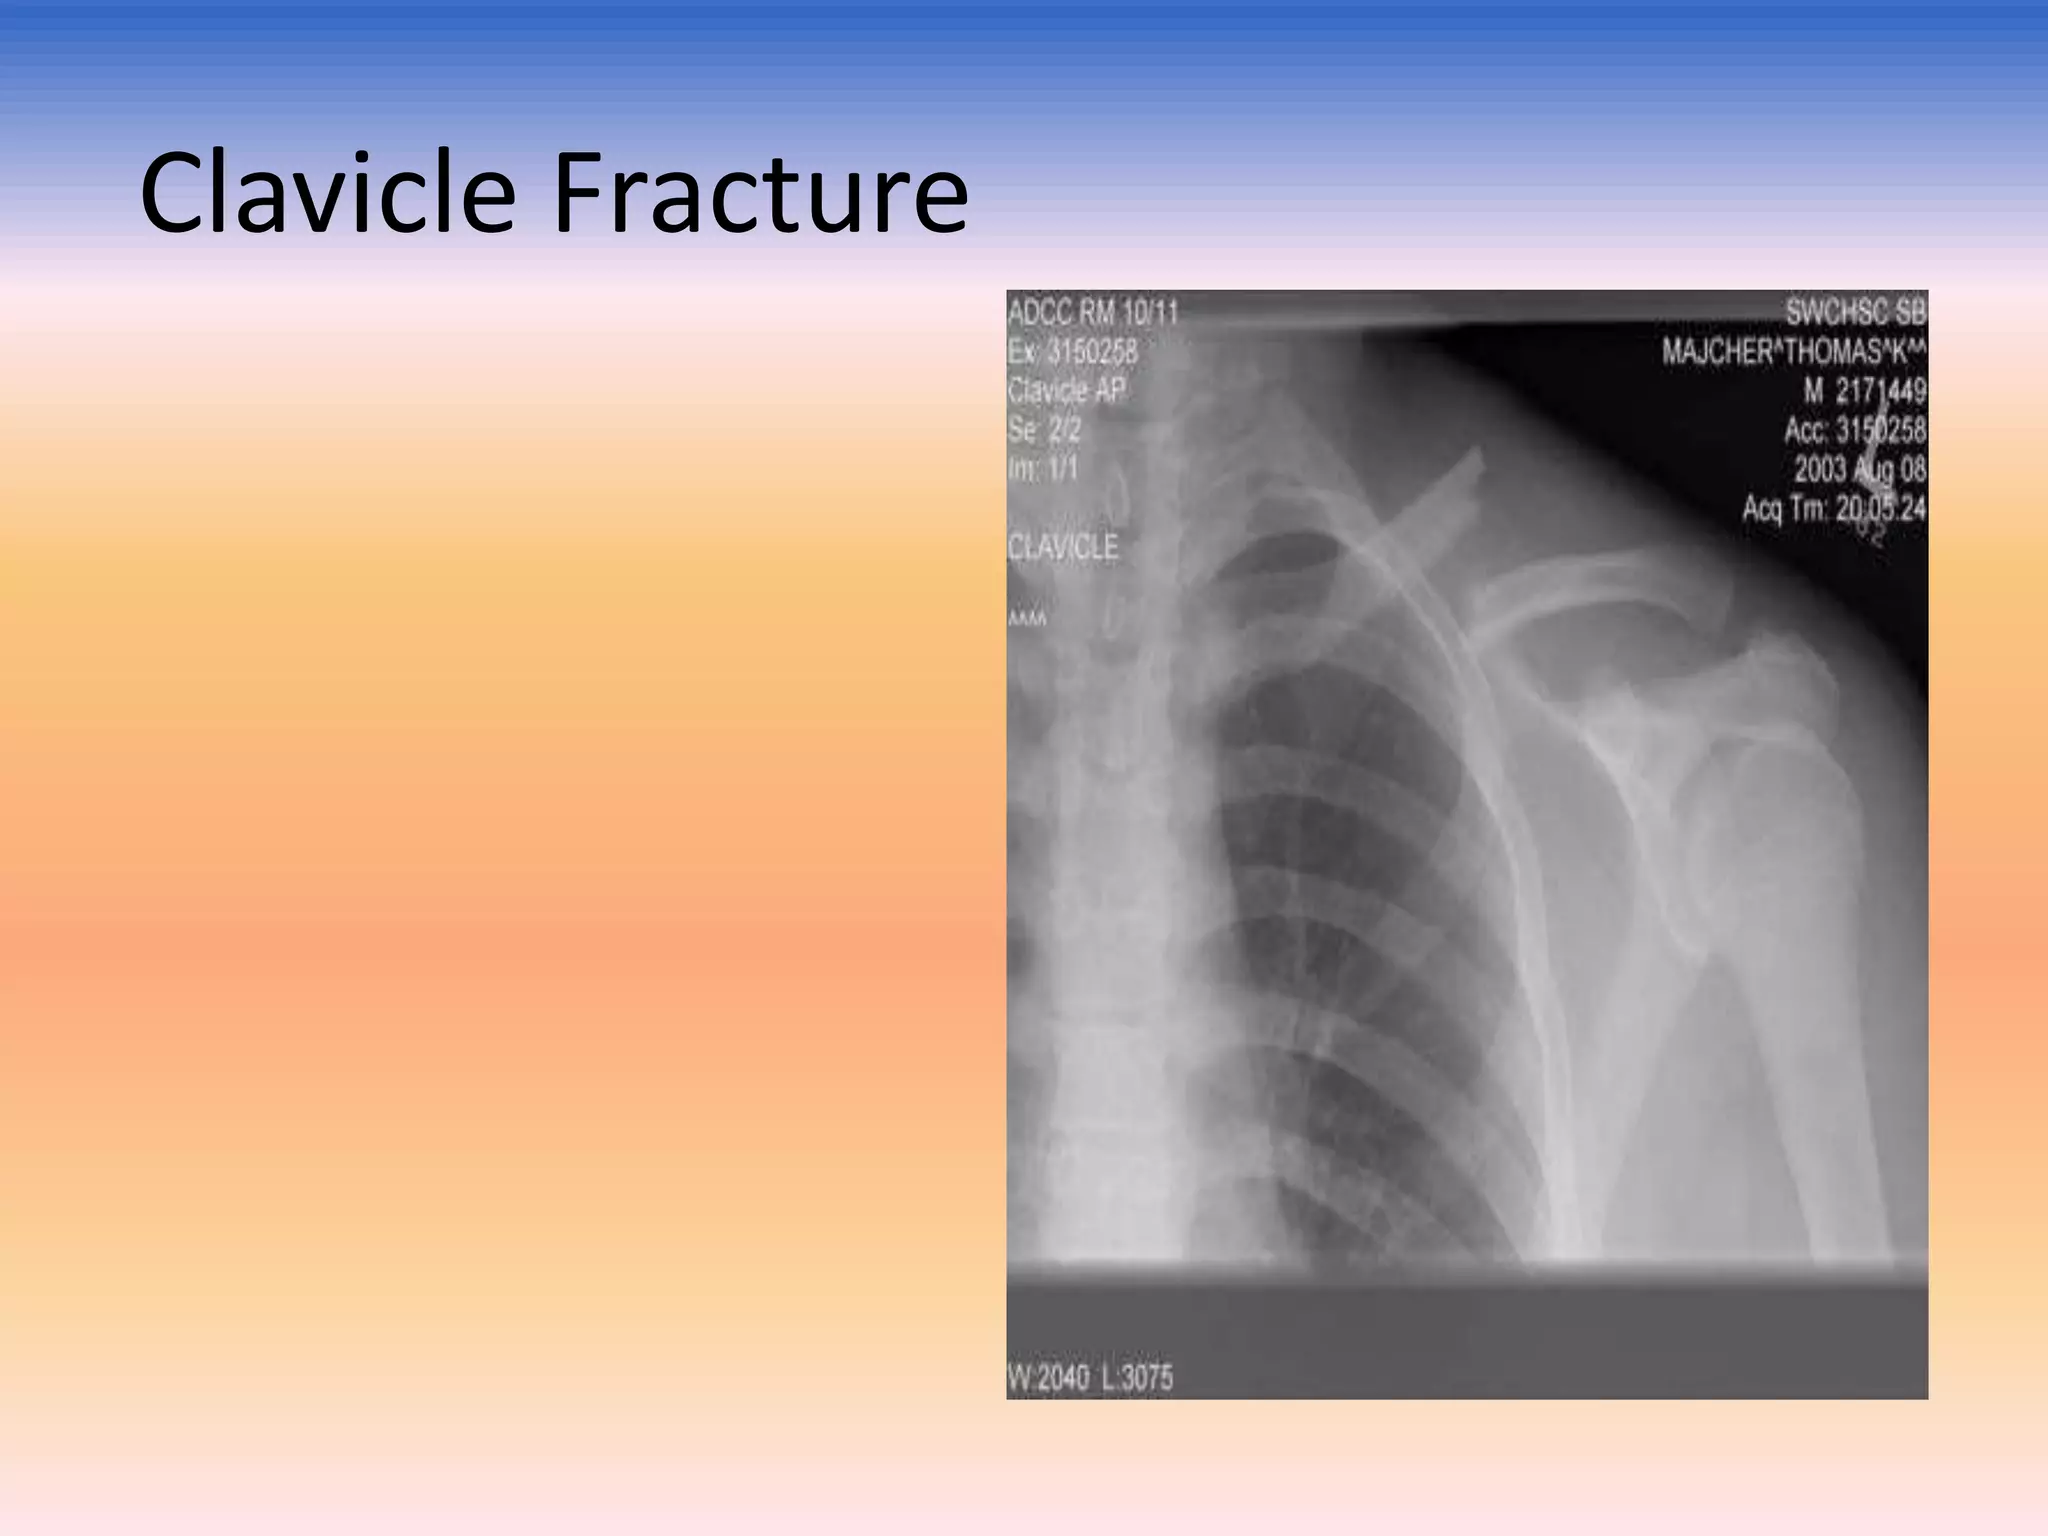

Clavicle Fracture